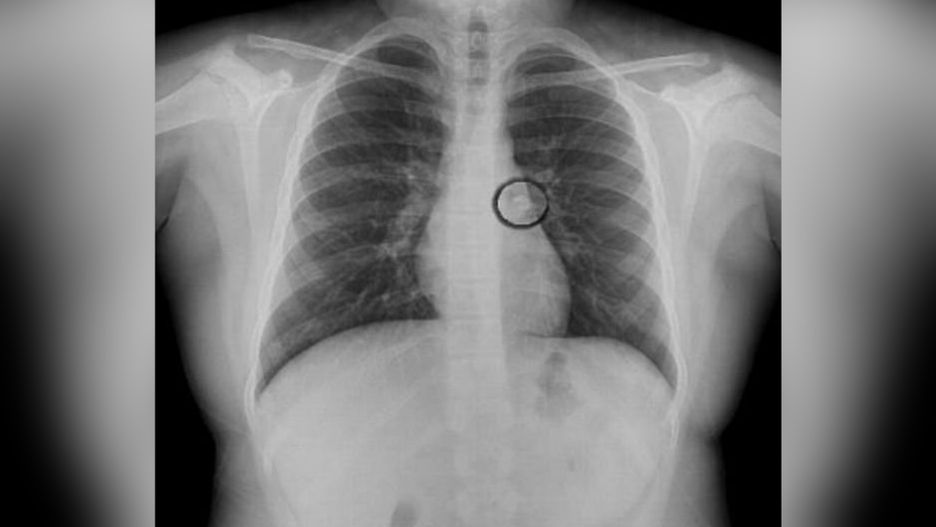

Podczas badań lekarz usłyszał szmer w lewym płucu dziewczynki. Zlecił wykonanie badania rentgenowskiego klatki piersiowej. Okazało się, że w oskrzelach tkwi ząb, który dziewczynka straciła w nocy. Podczas snu ząb przedostał się do jej dróg oddechowych. Wszyscy byli zaskoczeni tym widokiem.

Ząb utknął w oskrzelach dziewczynki

Ząb utknął w oskrzelach dziewczynki © dailymail.co.uk